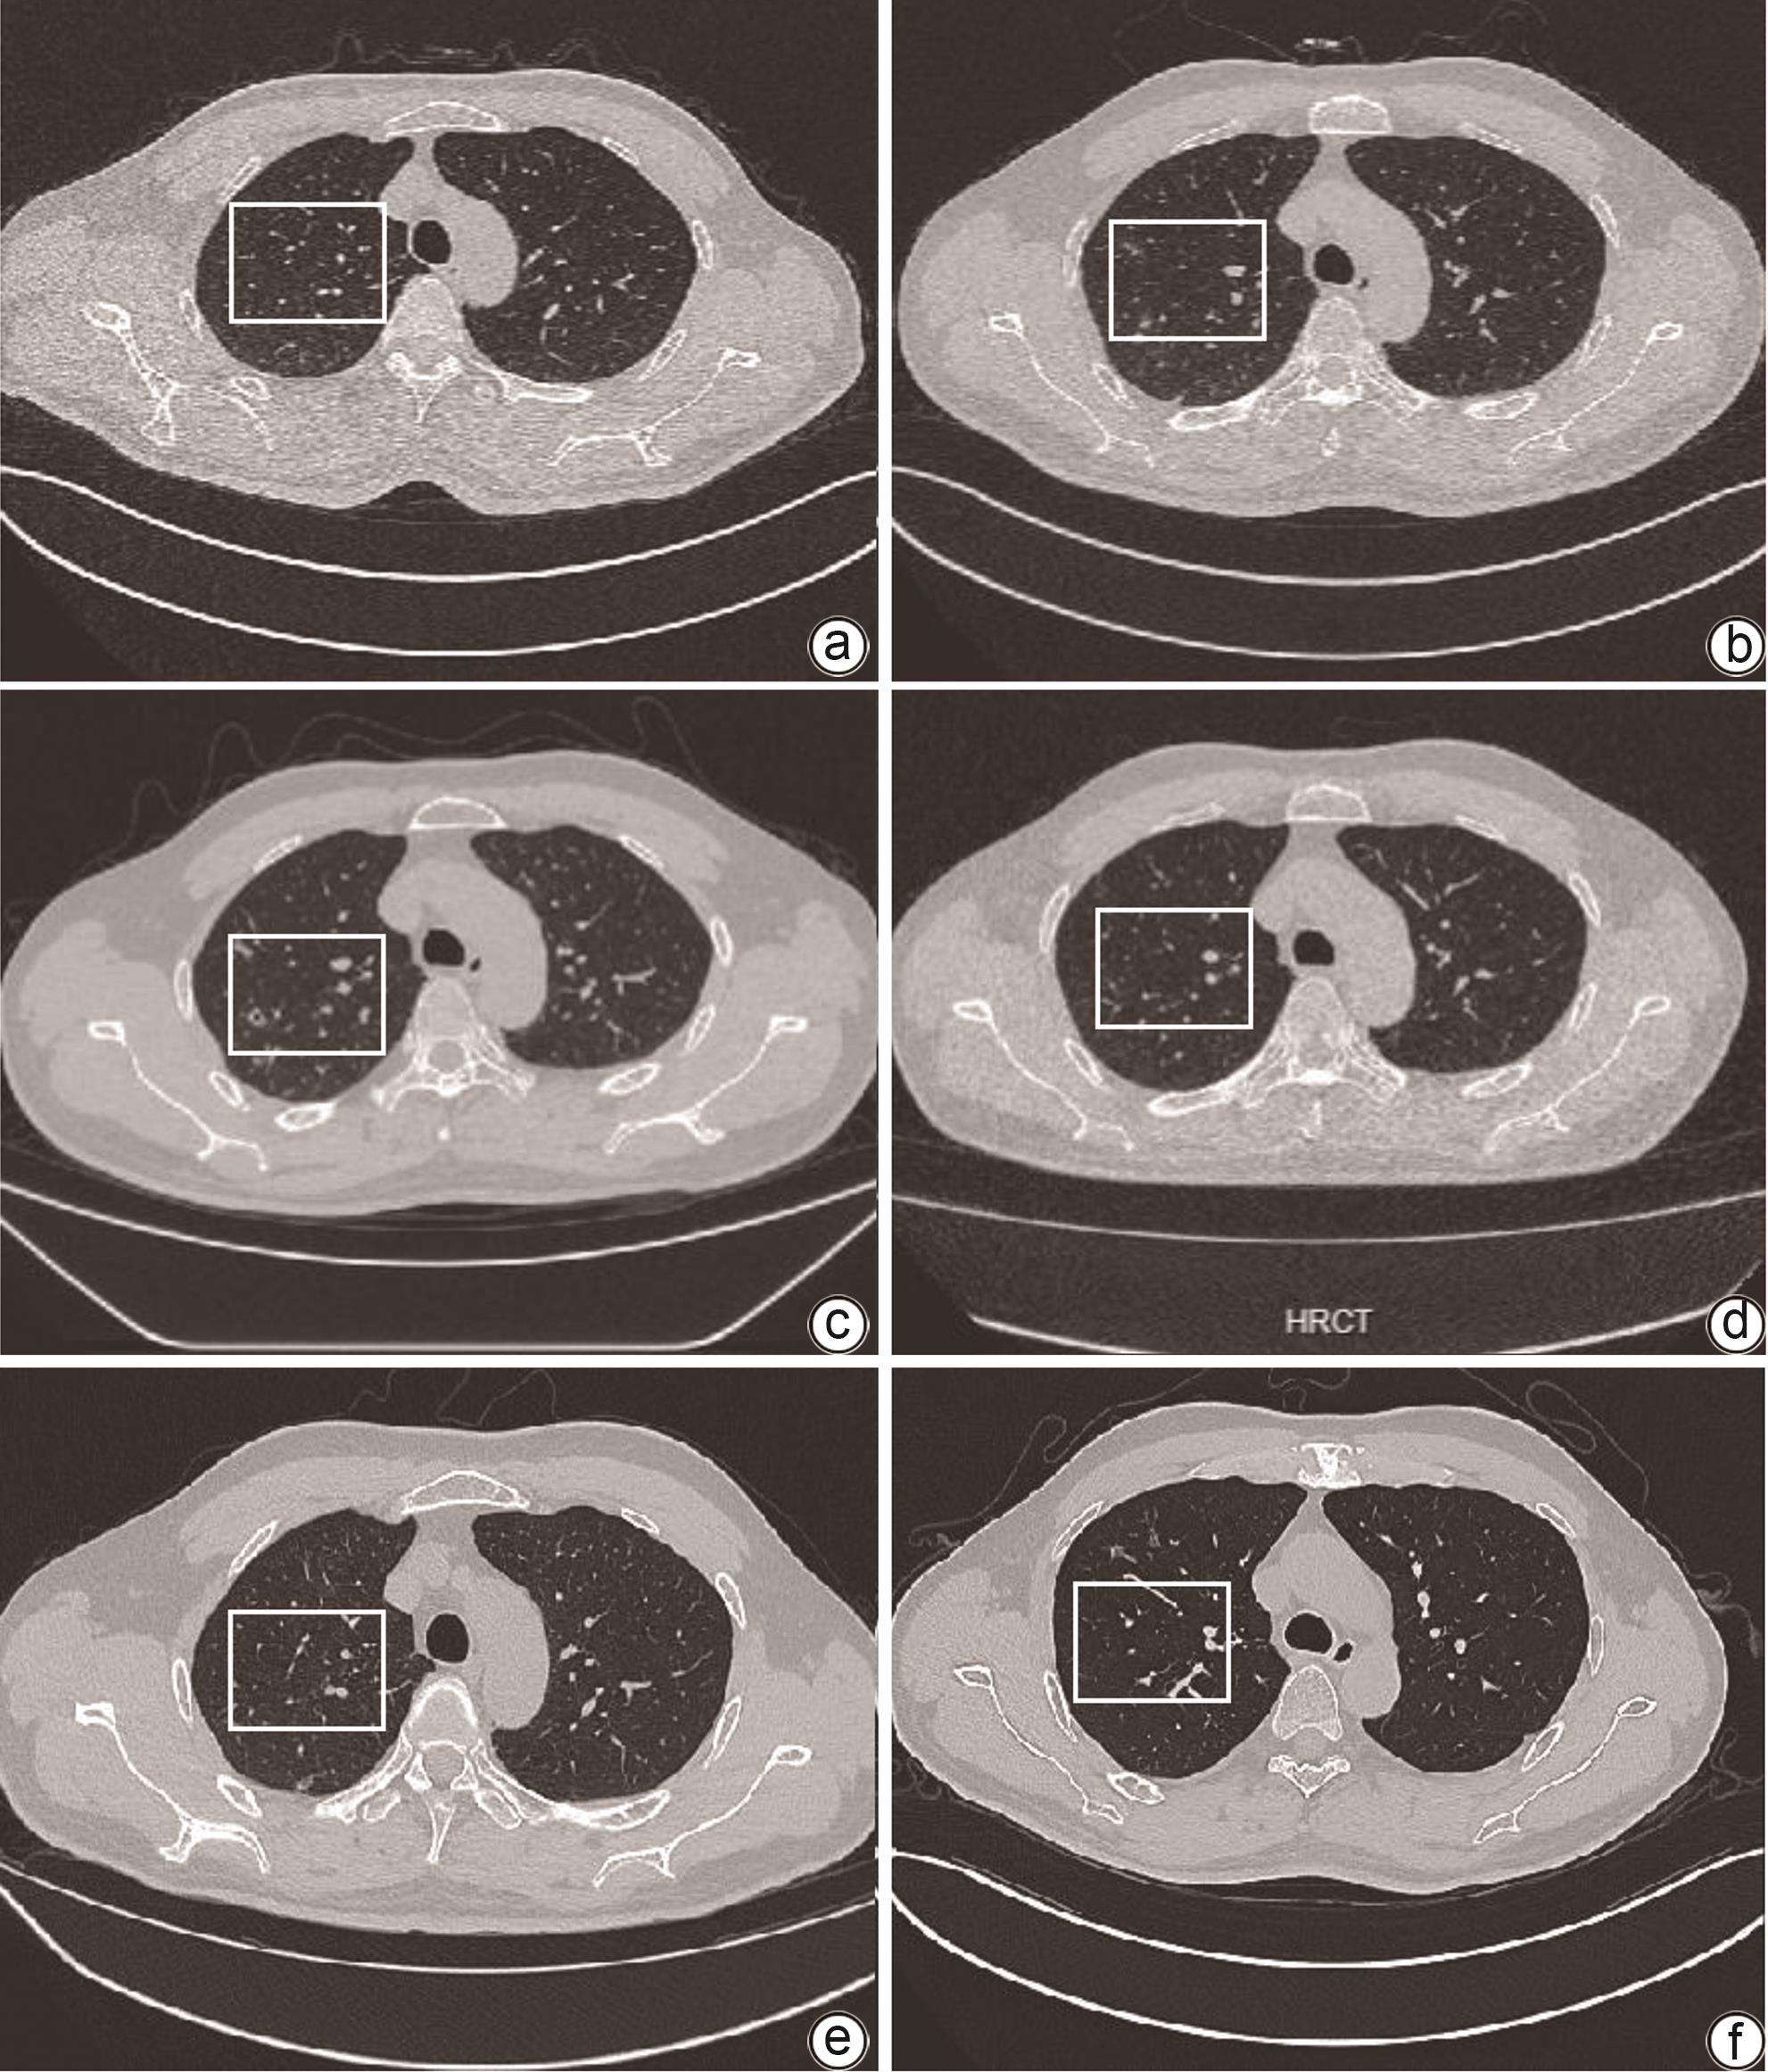

原发性胆汁性胆管炎-自身免疫性肝炎重叠综合征合并肺隐球菌病1例报告

张明明, 刘寰, 张冬梅, 吴东波, 唐红

2024, 40(8): 1666-1669. DOI: 10.12449/JCH240825

摘要(1016) HTML (358) PDF (1960KB)(90)

摘要:

自身免疫性肝病重叠综合征表现为患者出现一种以上的自身免疫性肝病的生化、免疫、组织学或胆管造影特征,常需联合使用免疫抑制剂治疗。肺隐球菌病是一种由新型隐球菌或格特隐球菌引起的侵袭性肺真菌病,易在免疫功能低下患者中发生。本病例为1例重叠综合征,在免疫抑制治疗过程中发现并治疗肺隐球菌病,在抗真菌治疗过程中肝功能出现异常,根据患者的肝功能情况,评估了更换抗真菌药物的可行性,综合考虑后制定了在密切监测肝功能的情况下,积极治疗新型隐球菌感染的治疗策略,避免了感染的进展。提示在启动免疫抑制治疗前,除了全面评估全身感染灶,对于可疑感染灶也必须保持监测。